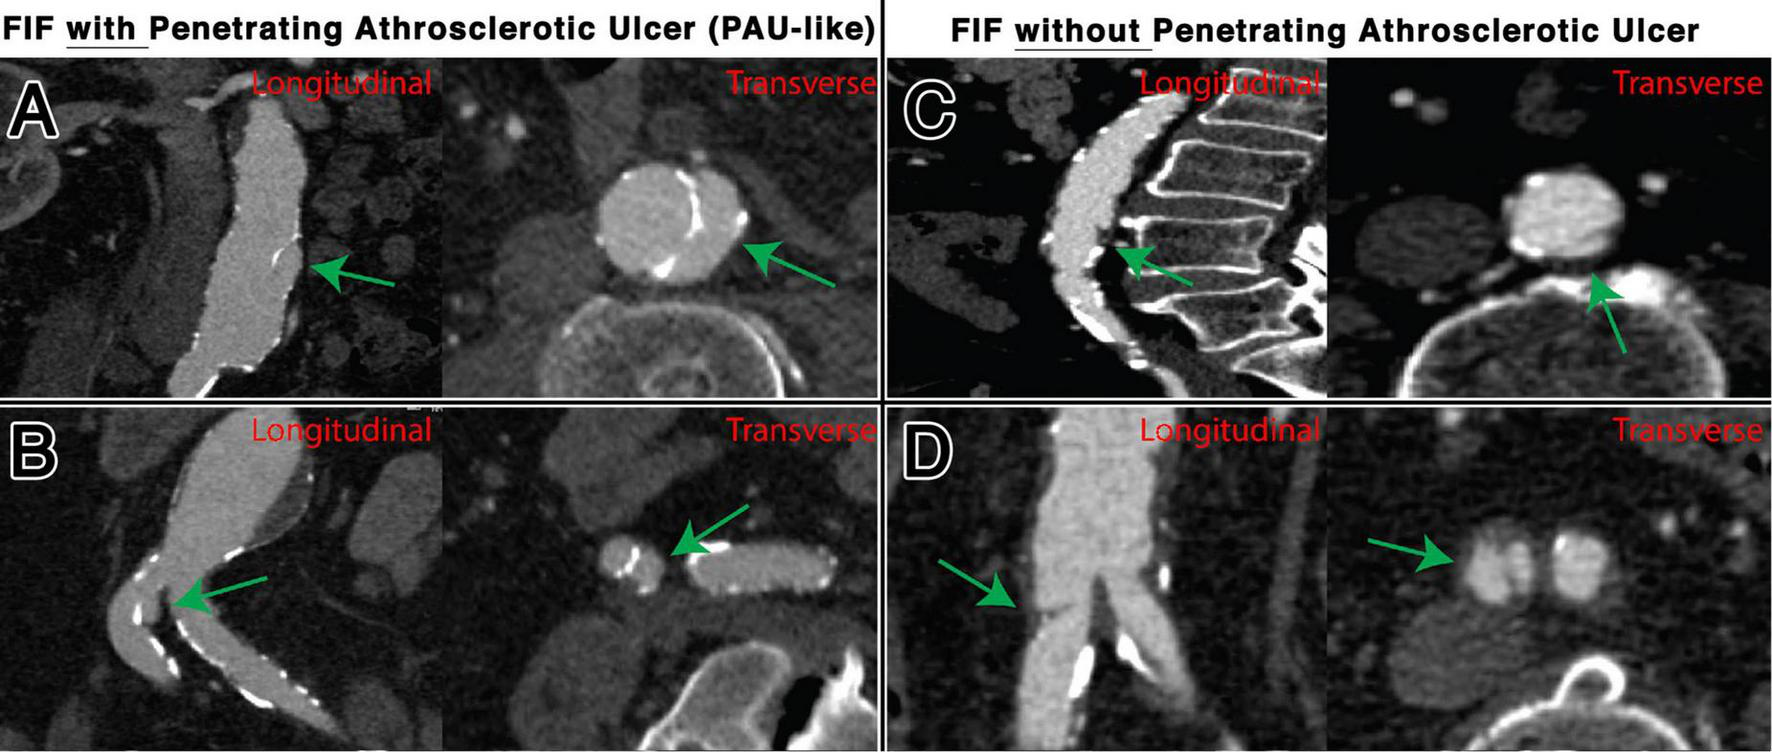

FIGURE 5

Representative examples of FIFs, with and without associated PAU, located in the abdominal aorta, shown transverse and longitudinal plane. Locations and characteristics of FIFs shown include infrarenal segment with PAU (A), common iliac artery with PAU (B), infrarenal segment without PAU (C), and common iliac artery without PAU (D).